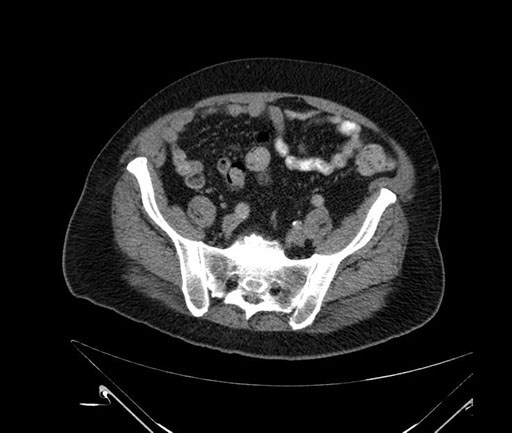

Imaging Analysis

Look through the patient's CT scan to identify any areas of concern for the necessary procedure.

Based on your CT findings, which issue(s) would give reason for "planned slowing down moment(s)" in this case?

Considering a standard Whipple procedure, what step(s) of the operation would you do differently in this case?